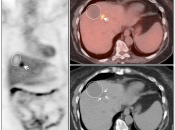

Radiofrequency Ablation of Liver Lesions

Although there is considerable variation in the recommended timing of PET/CT imaging after radiofrequency ablation of liver lesions, PET/CT has shown considerable utility for detecting recurrent/residual disease.

Some advocate post-procedure PET/CT imaging 24-48 hours after ablation to assure that the entire lesion has been fully treated (any remaining FDG uptake at this very early stage should represent residual active tumor, not post-procedural inflammation).

Later follow-up can then often performed, as clinically warranted (often at 3 and 6-months).

Benign Findings:

- Complete absence of metabolic activity in an ablated lesion is consistent with successful treatment.

- A homogeneous rim of well-defined peripheral hypermetabolic activity surrounding a non-avid hypodensity is presumed to represent post-ablation inflammatory changes.

The peripheral nature of this uptake is often best appreciated on the coronal images.

Recurrent/Residual Malignancy:

- Any nodular or focal uptake within or abutting the ablated lesion is highly suspicious for malignancy.